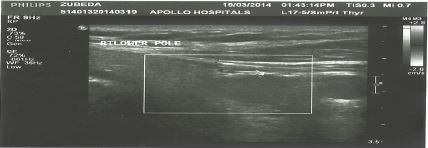

Investigation also showed serum calcium range from 2.85-3.0 mmol/L (2.13-2.63), phosphorus 0.7 mmol/L (0.8, 1.4) and magnesium 0.6 mmol/L (0.74, 1). The mean parathyroid hormone level (PTH) was above 30.4 pmol/L (1.69-6.9) or 198.5 pg/ml (15-65), which confirmed our suspicion of hyperparathyroidism. In addition the calcium to creatinine ratio was increased to 0.11 (normal limit < 0.06). Abdominal ultrasound showed multiple right renal calculi and mild hydronephrosis (see Figure 2); and neck ultrasound showed a low echogenic mass (1.3x1.5x3.3 cm) that intensified suspicion of a right inferior parathyroid adenoma (see Figure 3).

Figure 3: Neck ultrasound showing enlarged right lower parathyroid lobe

Figure 3: Neck ultrasound showing enlarged right lower parathyroid lobe